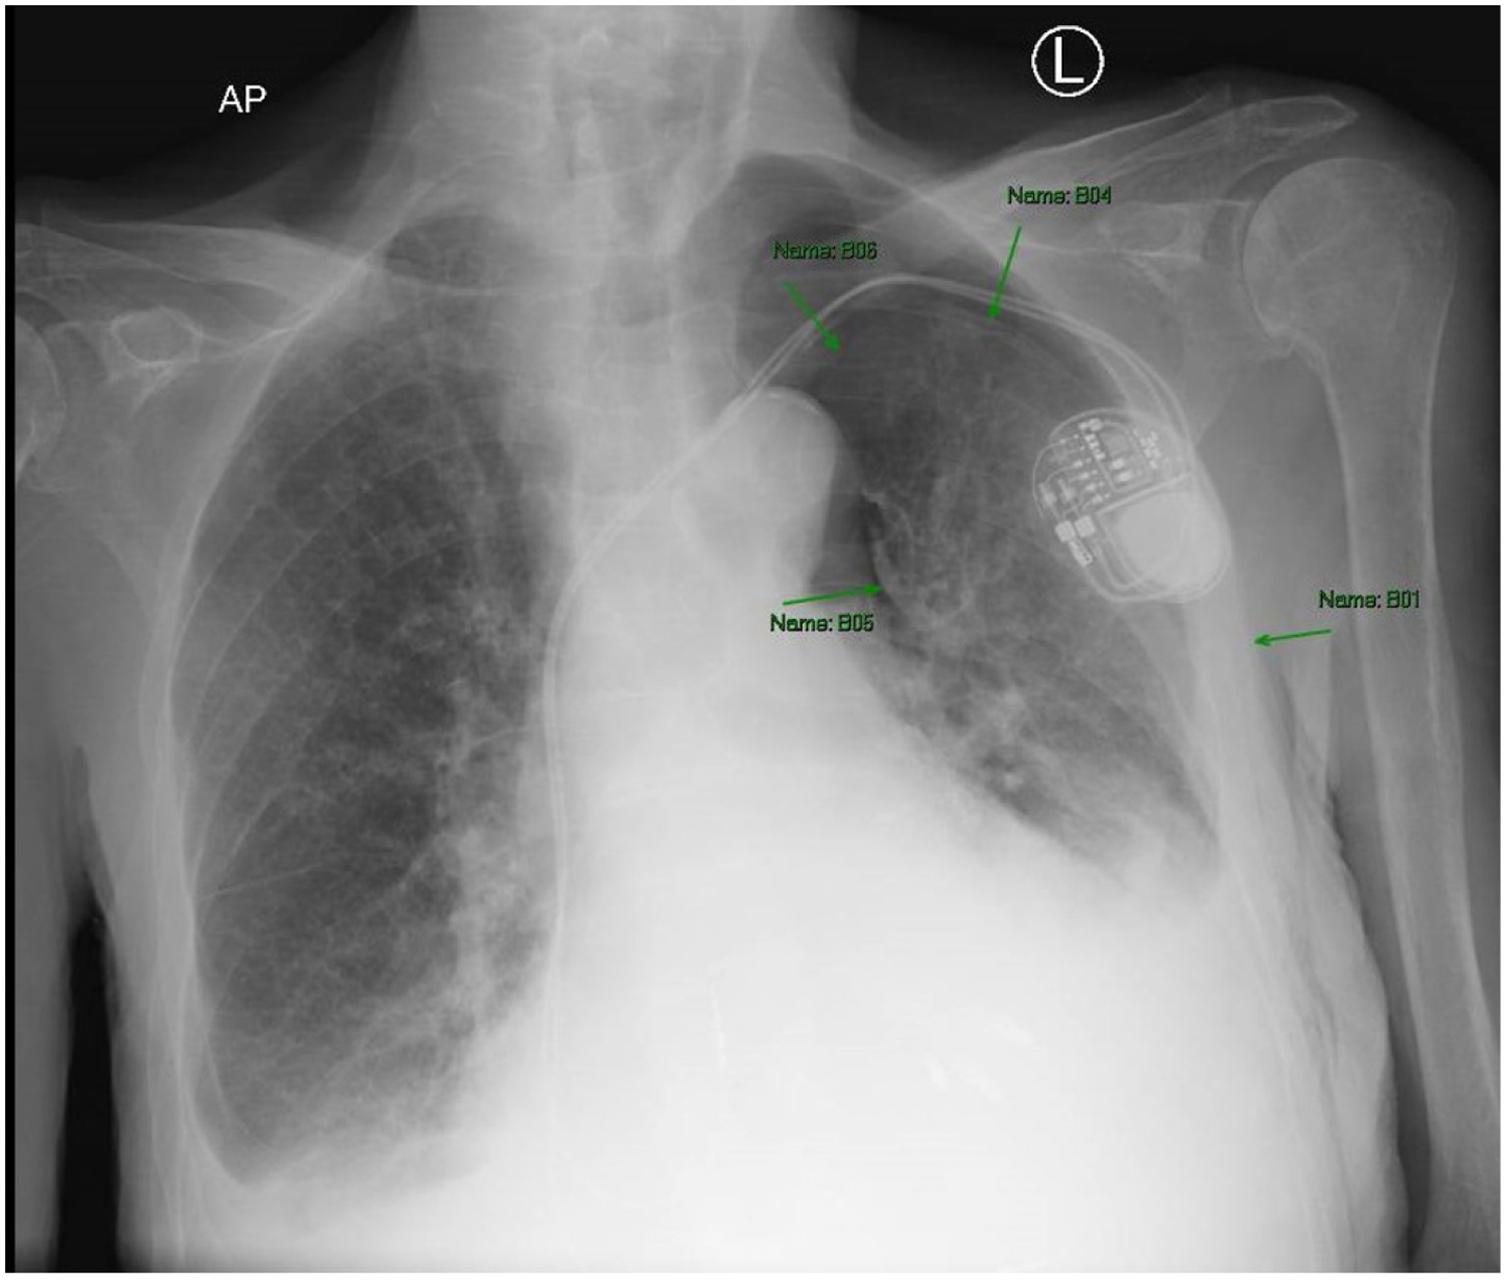

Initiallaboratoryresultsareshownin Table.An electrocardiogram(ECG)wasperformedandshowedasinus rhythmwithoutectopyorST-segmentchangesandwas unchangedfromhisprevioushospitalization.Chest radiography(CXR)wasobtained,shownin Image1.The radiologist’sinterpretationwas “[p]atchyopacityintheright lowerlobesuggestiveofpneumoniainthecorrectclinical setting.Goiterredemonstratedwhencomparedtoprevious. Normalcardiac findings.” Apoint-of-careultrasound (POCUS)oftheheartshowednopericardialeffusion,no suggestionofrightventriclestrain,novolumeoverload,and anormalleftventricle.

Image1. Initialchestradiographshowinganopacityintheright midlung(blackarrow)ina77-year-oldmanbeforeheexperienced arapidchangeinmentalstatus.

Lookingoverthelabsandimaging,Idonotbelievethey provideasignificantamountofnewinformationbutcouldbe usedtoremovesomedifferentials.Thepatient’schemistry hadsomeslightabnormalitiesbutnothingunexpectedgiven hiscomorbidities.Hiscoagulationstudieswereconsistent withsomeonewithcirrhosis.Thereweresomeabnormalities inhisthyroidfunctionpanel,butIdonotthinktheyexplain hisacutechange.Wealsodonotknowthetimingofhis levothyroxinedose,andhisthyroidstimulatinghormone indicatesthathehaslikelybeentakingit.Theetiologyof hematuriaisunclear,buthisurineisotherwisewithoutany signofinfection.Hiscompletebloodcountdoesshow leukocytosisaswellasmildanemia.Lastly,hisCXRis subtle,butanopacityintherightmidlung,asinterpretedby radiology,wouldbeconsistentwithhisabnormal breathsounds.